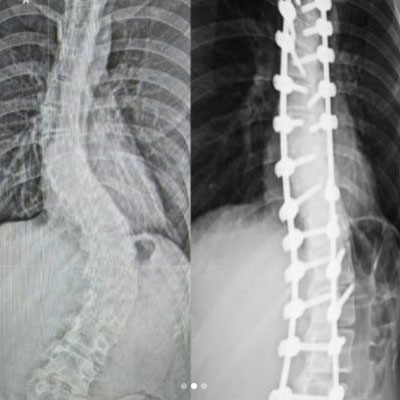

Kifoz, omurganın doğal kavislerinden biri olan torasik bölgedeki (sırt) normal kamburluğun aşırı artışıyla karakterize bir durumdur. Omurga normalde bel ve boyun bölgelerinde lordoz adı verilen içe doğru kavis ve sırt bölgesinde kifoz adı verilen dışa doğru kavisle şekillenir. Ancak, kifozun normalden fazla olması durumunda omurga, yuvarlak bir şekil alır ve sırt bölgesi yuvarlaklaşır. Bu durum genellikle postür bozukluklarından, kas zayıflığından, yaşlılık etkilerinden veya bazı hastalıklardan kaynaklanabilir. Kifozun şiddeti, belirtileri ve tedavi yöntemleri bireyden bireye farklılık gösterir. Fizik tedavi, egzersiz, ortez kullanımı ve nadiren cerrahi müdahale gibi yöntemlerle kifozun yönetimi amaçlanır.

Omurganın öne eğilmesiyle meydana gelen bir hastalıktır. Kamburluk doğuştan oluşabildiği gibi (Konjenital kifoz) sonradan da gerçekleşebilir. Kifoz hastalık olarak en çok sırt bölgesinde görülür. Bu bölgede normal kifoz açısının üst limiti 50 derece olup bu dereceyi aştığında hastalık düzeyinde kifozdan söz edilir.